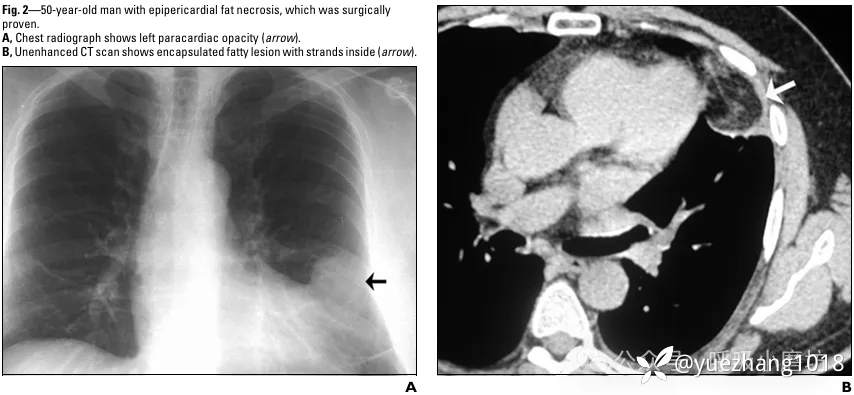

50岁男性患者,因“急性左胸痛3天”入院,疼痛随呼吸和体位改变加剧。

胸片见左心旁模糊影(图3A)。CT检查发现一边界清晰的脂肪性肿块,其内部可见致密条索影(图3B)。

图3A 胸部X线片显示左心旁高密度影(箭头所示);3B CT平扫显示被包裹的脂肪病灶,内部可见条索状影(箭头所示)

因不能完全排除脂肪肉瘤,患者接受了胸腔镜手术。

术后病理证实为“脂肪组织坏死伴炎细胞浸润”,未见肿瘤细胞。